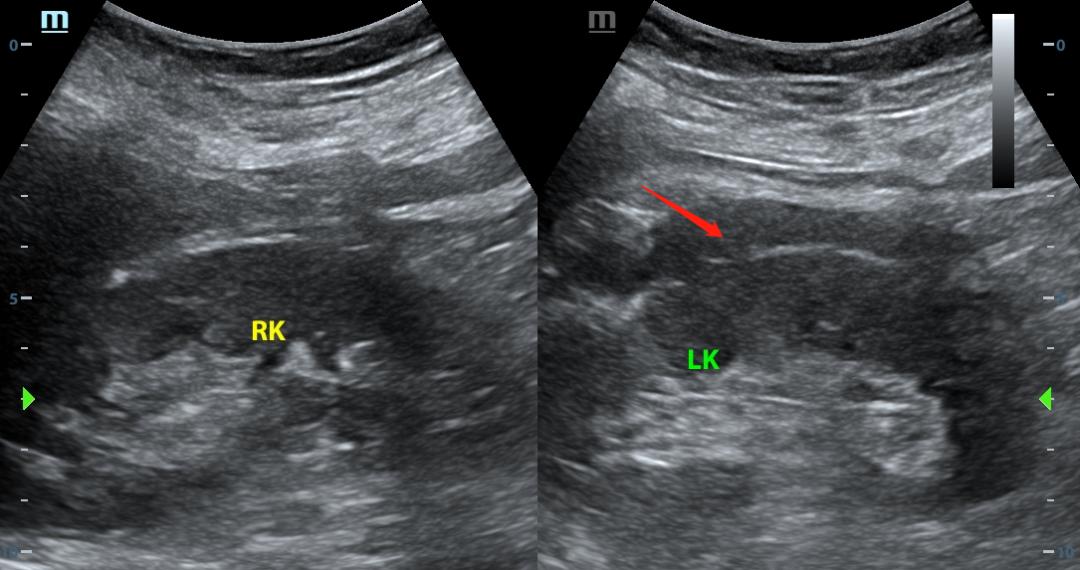

下图就是例子:

1、多切面

如果发现异常回声,至少两个切面都扫及了,才能确定有异常回声,如果一个切面扫及异常回声,有可能是异常的,也有可能就是个伪像,换个切面也许就一目了然。